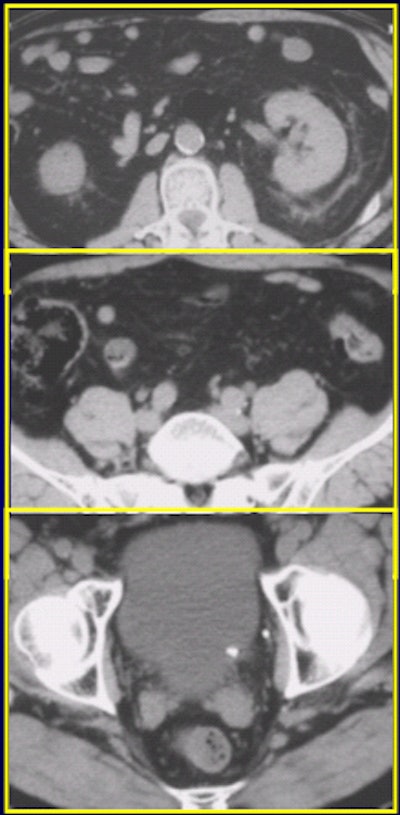

On 120 mAs (above) and 240 mAs (below), an extraurinary diagnosis of right hemorrhagic ovarian cysts and abdominal aortic aneurysm. Images courtesy of Dr. James Bell.

![]() |